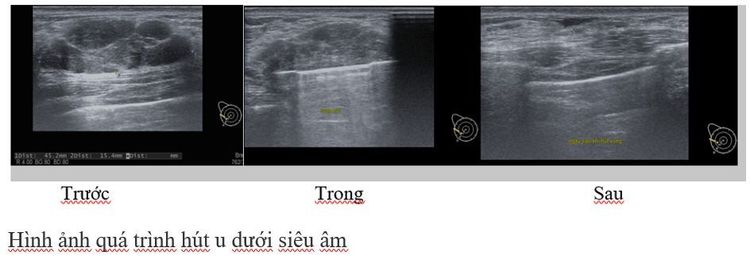

Dưới sự hướng dẫn của hình ảnh siêu âm, kim sinh thiết sẽ được đưa vào phía sau khối u tại vị trí 6h. Sau khi kiểm tra vị trí kim tốt, máng kim tốt, máy hoạt động tốt thì bắt đầu tiến hành cắt và hút u ra ngoài. Toàn bộ quá trình cắt –hút u vú lành tính của kim sẽ được bác sỹ quan sát theo thời gian thực dưới siêu âm, đảm bảo u được cắt hoàn toàn và không có biến chứng xảy ra.